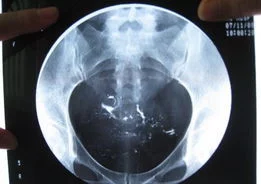

2)在X线透视下观察造影剂流经宫腔及输卵管情况并摄片。在荧光透视下徐徐注入碘油。注入量第一次为3~5ml,观察其进入子宫及流经输卵管的情况,此时摄片一张。继续推入碘油3~5ml,5~10分钟后拍片。

1. 输卵管通畅:子宫充盈呈倒三角形,两侧输卵管像细虫样弯曲在子宫两侧,造影剂先充盈输卵管近端的狭部,然后迅速向壶腹端部充盈,继而自伞端弥散至盆腔。

2. 输卵管阻塞:输卵管完全不显影或显影一段后不再显影,且造影剂注入到一定剂量时阻力加大,盆腔内无造影剂影弥散。

3. 输卵管通而不畅:推注造影剂有阻力,造影剂进入盆腔缓慢,在停注造影剂十数分钟后,可见造影剂在盆腔内弥散,但弥散欠佳。

4. 输卵管积水:造影剂积聚在输卵管内,输卵管异常扩张呈囊状或腊肠状,以远端明显,多伴有输卵管伞端阻塞。盆腔内一般无造影剂影弥散,

5. 输卵管伞端周围粘连:造影剂可以进入腹腔,但积聚在输卵管伞端周围.,弥散不佳。